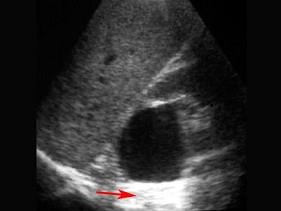

问题 红色箭头所指部位是?(?)

选项 A.后部回声增强 B.声影 C.无回声 D.强回声 E.等回声

答案 A